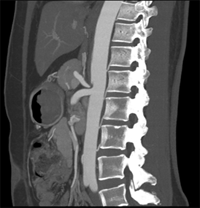

同一病人利用容積數據進行三維處理后,高品質MPR和三維圖像上則清晰顯示了縱向排列的腹腔干與腸系膜上動脈相鄰近,血管發生變 異,近端血管閉塞,為臨床提供了精確的診斷信息。